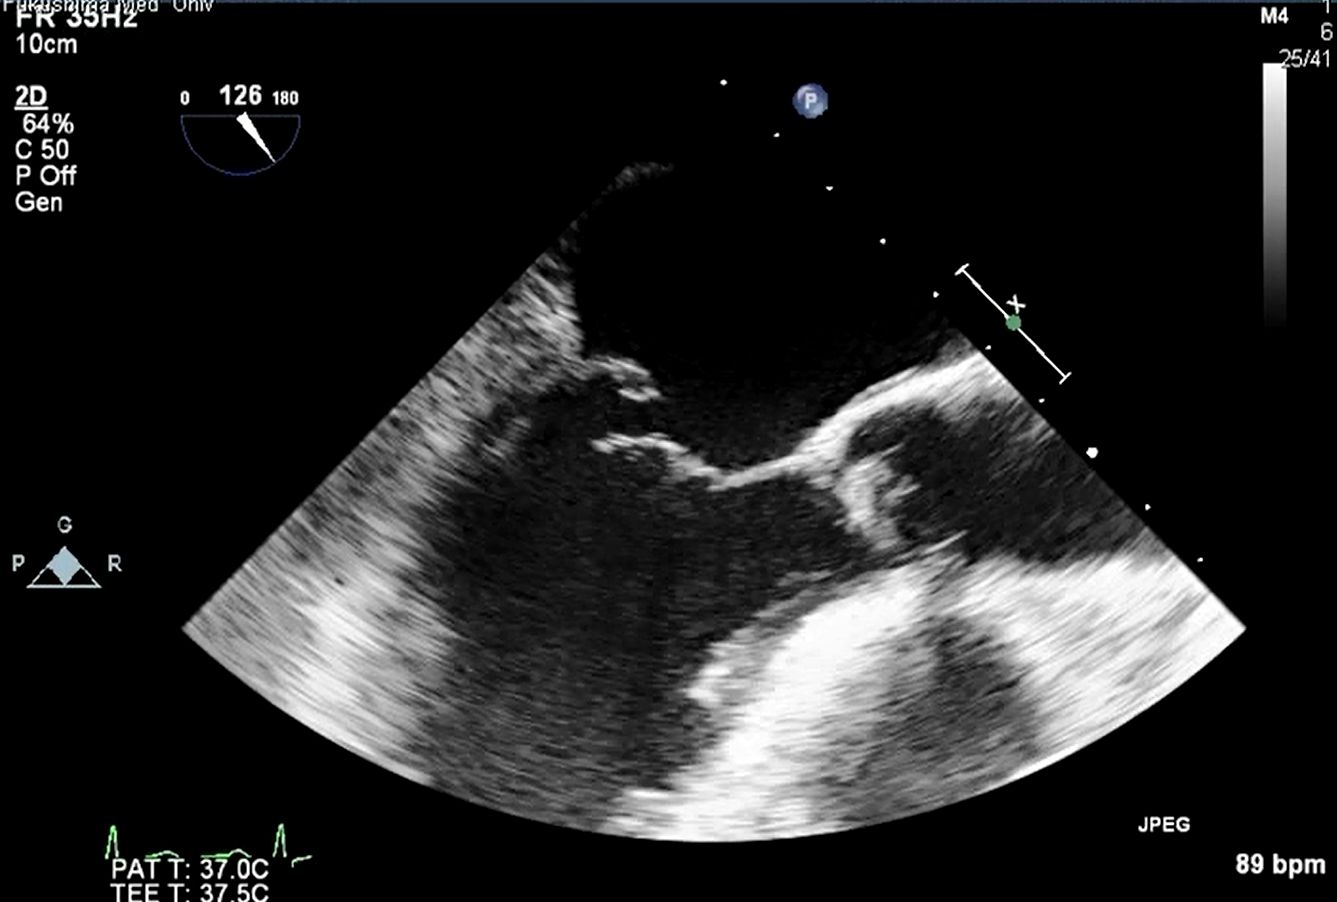

経食道心エコーは、超音波探触子を食道内に挿入して心臓を観察する検査で、体表面では評価困難な弁の性状や左房内の血栓などをより鮮明に評価が可能です。当科では、毎週2回(水、木)施行しております。当院エコー室で使用している、経食道エコーの探触子は3Dエコーの表示が可能で、より詳細に弁や欠損孔等の観察が可能です。

僧帽弁逸脱症候群

左心耳血栓